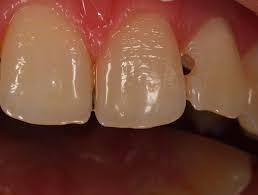

Wypełnienia – uzupełnianie brakujących tkanek zęba/ubytków materiałem kompozytowym w kolorze zęba .

ubytekmaly

Ubytek mały

ubytek duzy

Ubytek duży